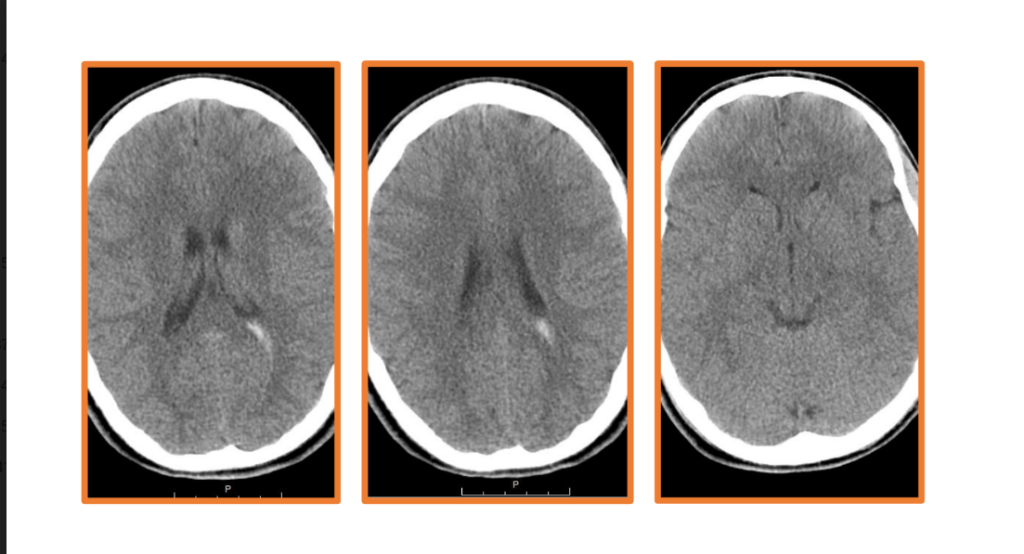

Here I have some CT and MRI images taken soon after my injury. The blurred parts of the MRI image towards the center show evidence of shearing. In addition, the bright white portions of the CT images represent accumulations of blood, known as hemorrhages. These also contributed to the extent of my injury. Had the emergency staff not implanted what is known as an intracranial pressure cup (ICP) to relieve the pressure from the excess fluid within my cranial cavity, my brain would have been displaced and squished down by the fluid, and the extent of my injury would have been much worse, potentially even fatal.